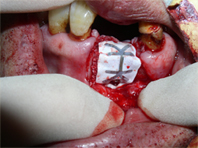

歯茎を切開して拡げてみると骨がなくなっています。

歯を抜いた部分にインプラントを埋入するが、骨がなく、インプラントがほとんど見えている状態です。

骨のない所に、骨に置きかわっていく補填材を移植します。

(自家骨:インプラントを埋入の為にドリルで切削中に集めた骨や顎の部分から削った骨を予め集めておいたもの)

骨補填後に、崩れないようにその部分をカバーするように特殊な膜やプレートでおおい、その後縫い合わせます。